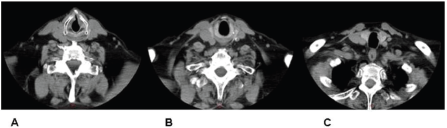

Imaging confirmed the laryngeal lesion, yet it also indicated a second lesion about 2 cm below the inferior end of the primary one, arising somewhere between the first and second tracheal ring. Intermediate tissue appeared grossly normal (Figure 1). No signs of enlarged cervical lymph nodes were noted and laryngeal cartilages showed no abnormal findings.

Figure 1. CT indicating both glottic (A) and tracheal (C) tumours. Intermediate tissue appears grossly normal (B).